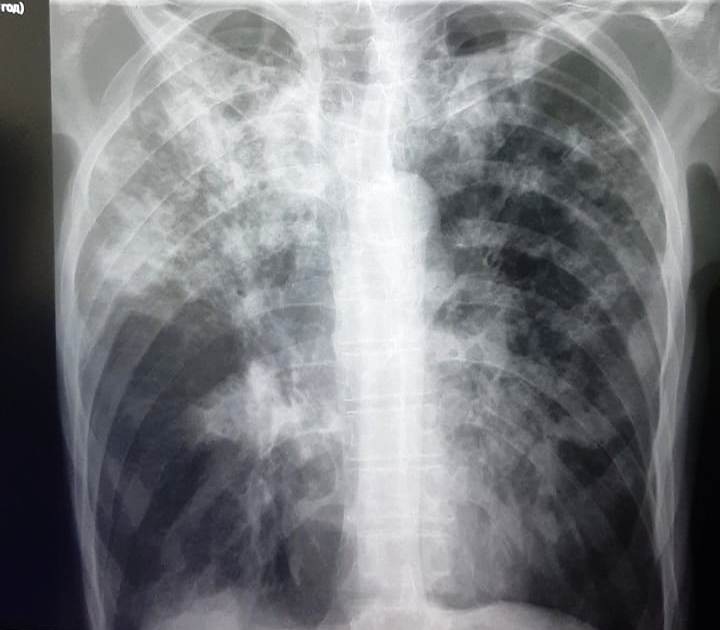

Туберкулез – это опасное заболевание, которое вызывается бактериями Микобактерия туберкулеза и может поражать любые органы человеческого организма. Эта болезнь является одной из самых распространенных в мире и прежде всего угрожает жизни людей с ослабленным иммунитетом. Но что такое туберкулез и как его лечить?

Заболевание может проявляться в разных формах: от скрытой до открытой, с выделением бактерий в окружающую среду. Основным симптомом туберкулеза является постоянный кашель, выраженный утром, с наличием мокроты. Другие часто встречающиеся симптомы - потеря веса, потливость, повышение температуры тела и слабость.